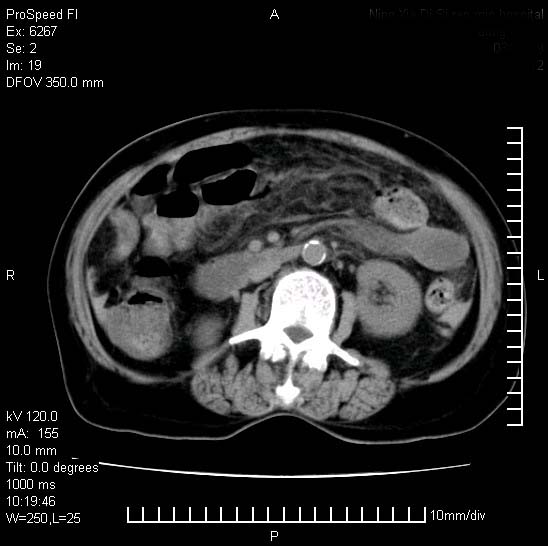

患者糖尿病,腹痛,恶心,呕吐。黄疸,意识较差,血糖很低(数值不详),临床以胆囊,胆管炎,低血糖反应收治。看的腹片少,各位帮忙看看,胰腺有问题吗??

1.胰腺体积增大,胰周脂肪间隙消失,胰腺炎可以确定。必要时实验室进一步检查。

胰腺体积增大,胰周脂肪间隙消失,考虑胰腺炎。胆囊炎,胆石症。

脾大,原因?胆结石;胰腺肿大,边缘模糊,建议查定性指标血尿淀粉酶,除外胰腺炎

1)考虑胰腺炎;建议查血尿淀粉酶。2)胆囊炎,胆囊结石。3)脾大。